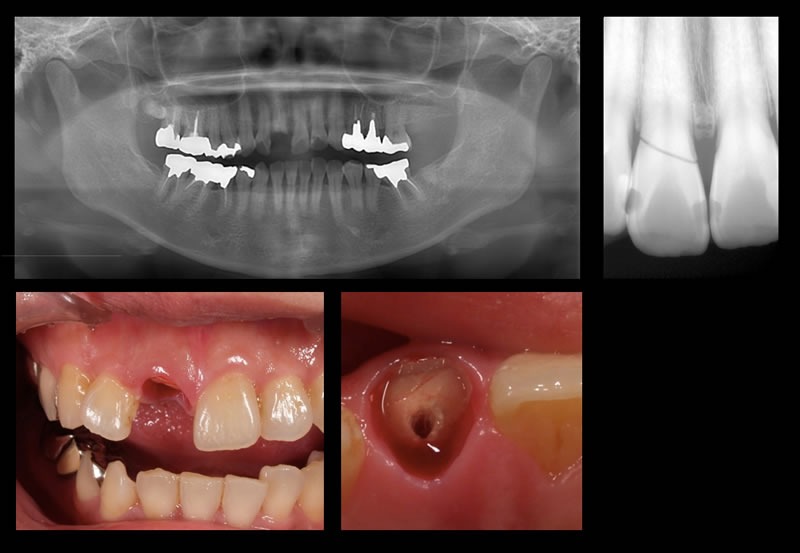

右の前歯が折れた

初診時

右の前歯が折れた状態で来院。